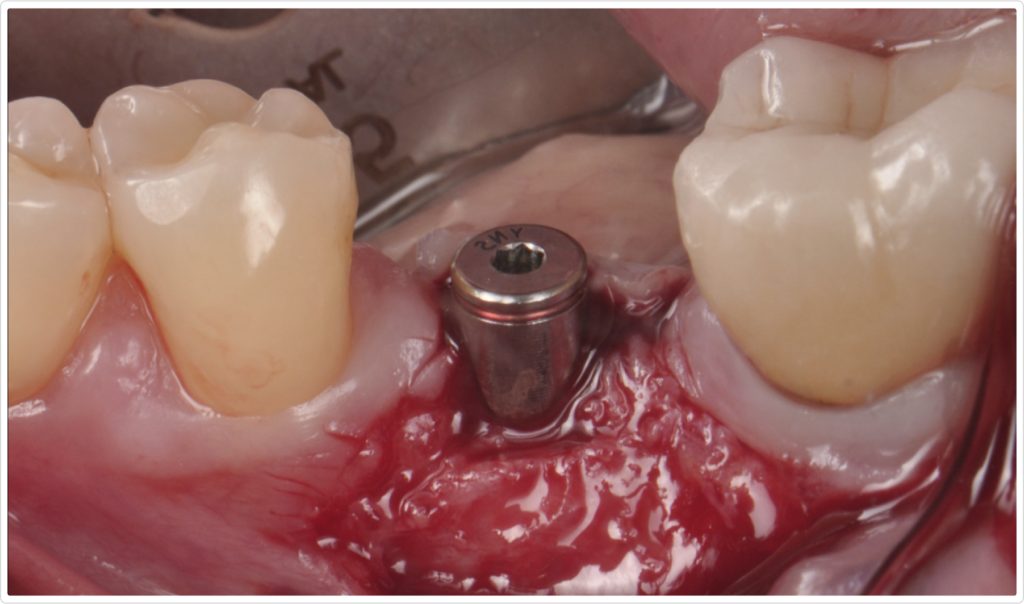

To address the deficiency in keratinized mucosa, a second-stage surgery was planned. A crestal incision was made at the edentulous site, not touching the adjacent teeth. A partial-thickness flap dissection was performed at the implant site, displacing the minimal keratinized tissue present at the lingual site (Fig. 9). Two divergent vertical incisions were made at the buccal area, leaving the connective tissue and periosteum attached to create a vascular surface for a free epithelialized graft. The cover screw was then removed, and a 5 mm healing abutment was placed.

Graft harvesting and placement

A free epithelialized graft was harvested from the anterior palate and fixed in place with 6-0 polypropylene simple interrupted sutures at the edges and a periosteal suture around the healing abutment. Additional 5-0 simple interrupted sutures were used to secure the flap in an apical position, ensuring optimal adaptation and stability of the graft (Fig. 10). The donor site was treated by means of collagen sponges and crisscross 4-0 PTFE sutures anchored to the teeth, achieving hemostasis.